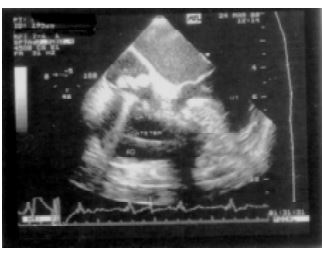

La infección de los catéteres marcapasos cardíacos definitivos (MCD) es una complicación poco frecuente pero su presencia puede asociarse con septicemia, endocarditis infecciosa (EI), embolias pulmonares o trombosis de las cavidades derechas. (1, 2) La severidad de estas complicaciones hace necesaria la utilización de métodos de diagnóstico de alta sensibilidad y especificidad. Se presenta el caso de un paciente, quien luego de un reemplazo de marcapasos cardíaco definitivo evoluciona en forma tórpida y en quien el ecocardiograma transtorácico (ETT), a pesar de tratarse de una alteración de cavidades derechas, es absolutamente negativo y, en cambio, en el ecocardiograma transesofágico (ETE) se halló un compromiso bacteriano difuso de los catéteres. Siguiendo normas aceptadas en la actualidad se procedió al retiro del sistema mediante cirugía cardíaca a cielo abierto y circulación extracorpórea (CEC) y a la implantación de un MCD con electrodo epicárdico. En esta presentación se destaca la importancia tanto del ETE en el diagnóstico de esta patología como de la implementación de una terapéutica agresiva.